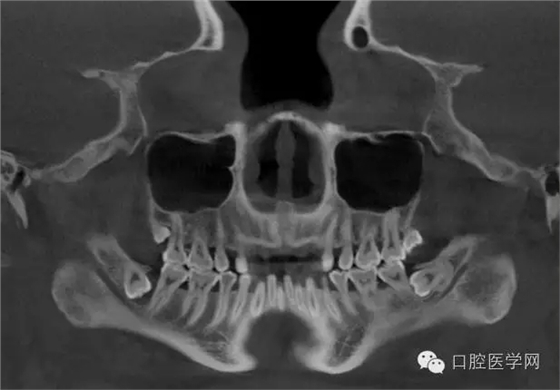

3.牙齒數(shù)目異常

額外牙

X線表現(xiàn):最多見于上頜兩中切牙之間;圓錐形,根短小;拍攝X線片可確定額外牙的數(shù)目、位置、形態(tài)與鄰牙的關(guān)系。

先天缺牙

X線表現(xiàn):常為對(duì)稱性;確定缺牙數(shù)目。